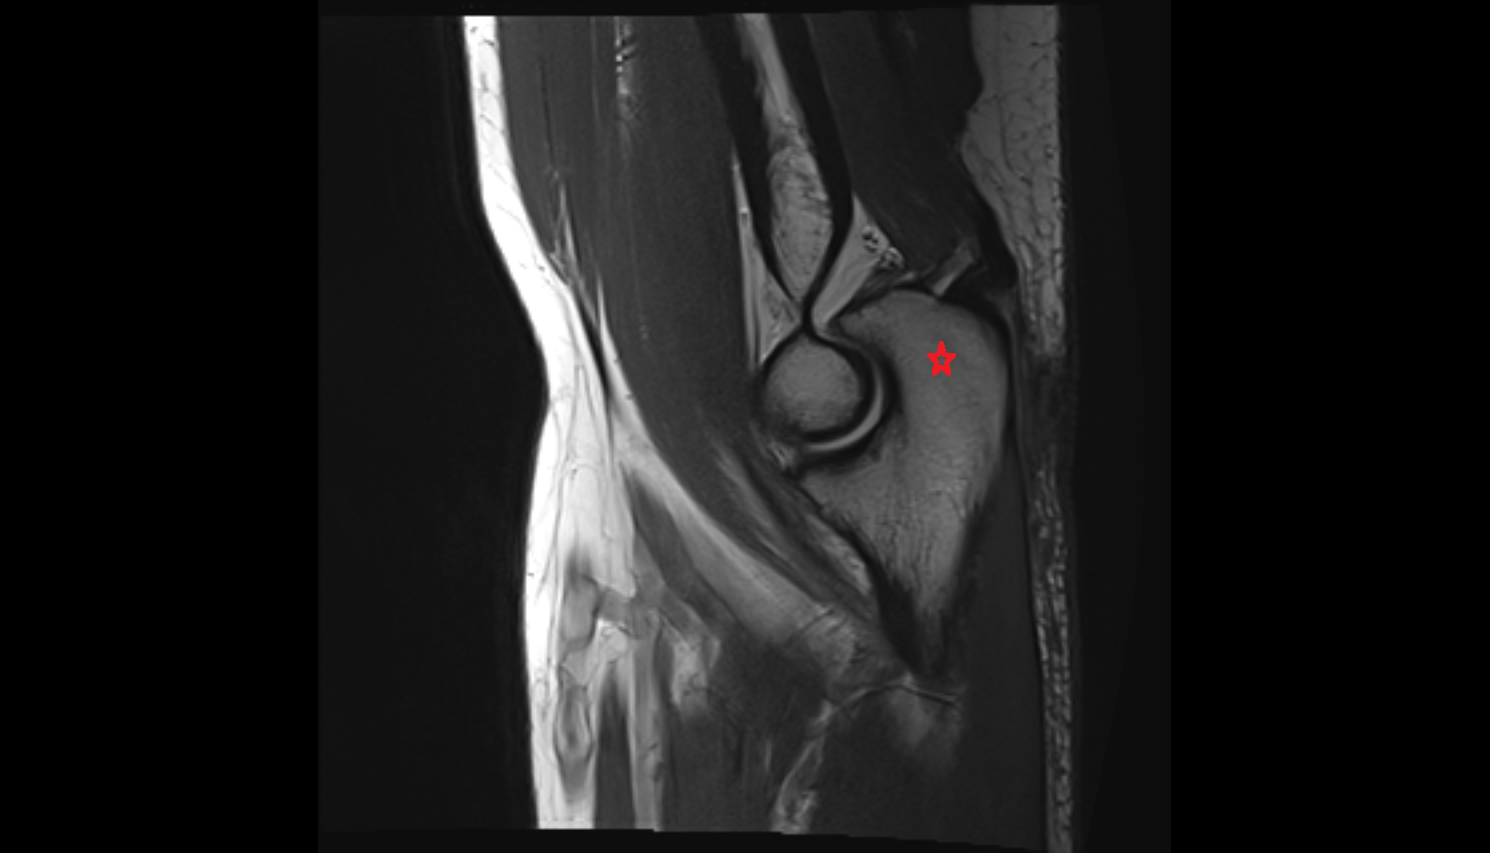

- Elbow joint

- Olecranon

- Coronoid process of ulna

- Capitulum of humerus

- Trochlea of humerus

- Head of radius

- Neck of radius

- Joint capsule of elbow

- Annular ligament of radius

- Radial collateral ligament

- Lateral ulnar collateral ligament

- Lateral collateral ligament complex of elbow

- Medial collateral ligament of elbow (anterior bundle)

- Medial collateral ligament of elbow (posterior bundle)

- Medial collateral ligament of elbow (transverse bundle)

- Medial collateral ligament complex of elbow (ulnar collateral ligament)

- Triceps brachii tendon

- Common extensor tendon

- Common flexor tendon

- Biceps brachii tendon (distal)